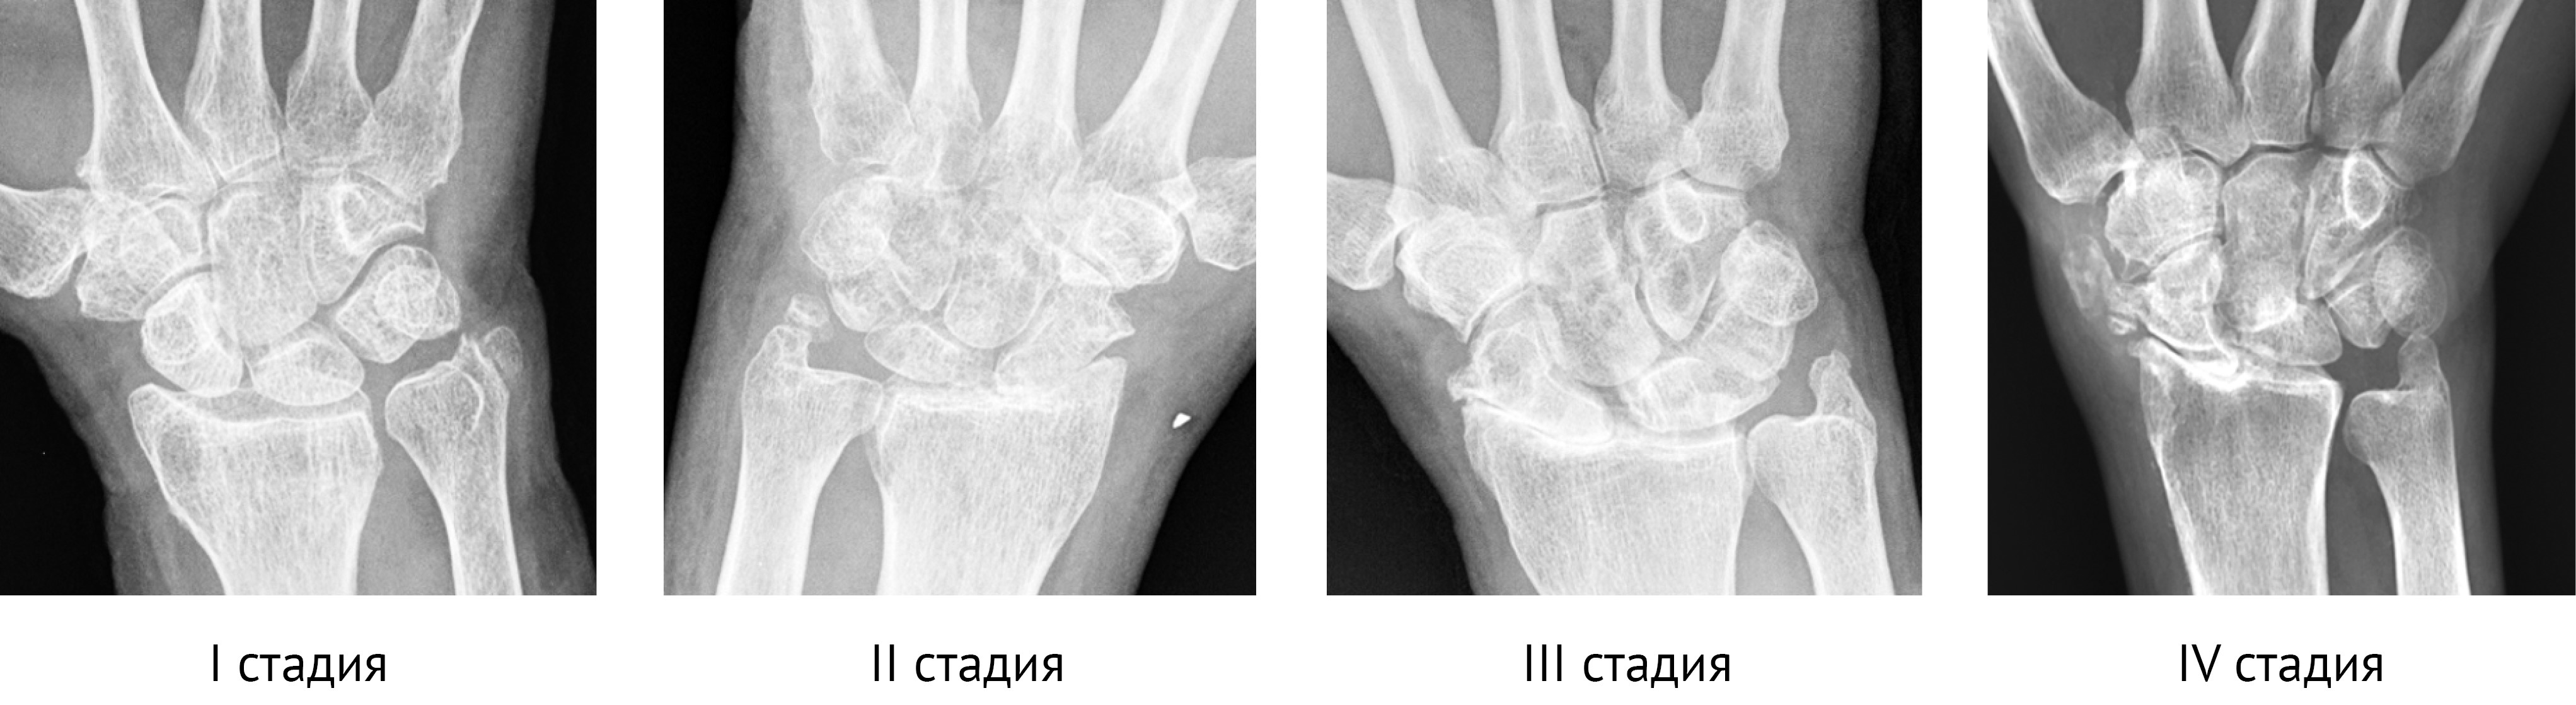

В течении SLAC выделяют три рентгенологические стадии [4, 23], по данным других авторов — четыре [24] (рис. 1).

Рис. 1. Фрагменты рентгенограмм кисти пациентов с разными стадиями SLAC в прямой проекции

Figure 1. X-ray fragments of patients´ wrists with various SLAC stages in the AP view

I стадия — поражены проксимальная часть ладьевидной кости и шиловидный отросток лучевой. На рентгенограммах в прямой проекции и на КТ на лучевой стороне ладьевидной кости и шиловидном отростке лучевой кости выявляются «острые подпорки» («клювы»), утрачивается нормальная округлая кривизна шиловидного отростка, развивается локальный артроз ладьевидной фасетки.

II стадия — поражение луче-ладьевидного сустава, прогрессивное сужение щели луче-ладьевидного сустава, склероз всей ладьевидной фасетки дистального луча.

III стадия — поражение головчато-полулунного сустава со склерозом и сужением суставной щели. При этом происходит проксимальная миграция головчатой кости со смещением полулунной кости в локтевую сторону.

IV стадия — дегенеративный артроз полулунно-лучевого сустава.